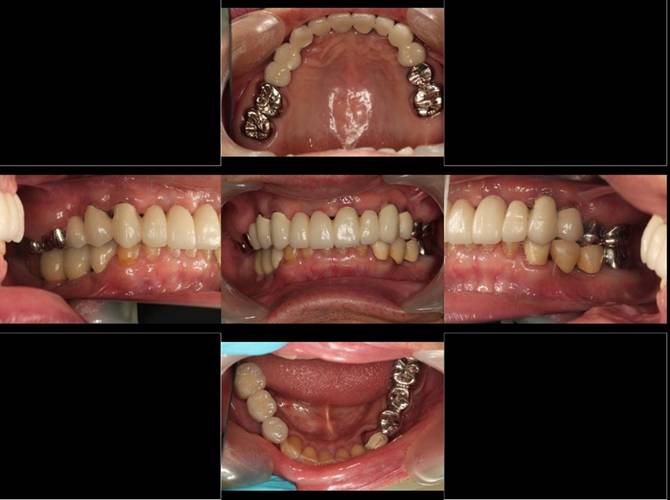

術後。上部構造はハイブリッドレジンです。しっかり嚙めるようになり喜んでいただきました。

下顎

上部構造装着後6年。ハイブリッドレジンを使用したため、少し艶がなくなってきました。上部構造の材料には金属、ハイブリッドレジン、セラミックなどがあります。セラミックはきれいですが欠けやすいため、最近はフルジルコニアを使っています。

下顎。12か月に一度メインテナンスをしています。

インプラント装着後6年。順調に経過しています。12か月毎のメインテナンスをしています。